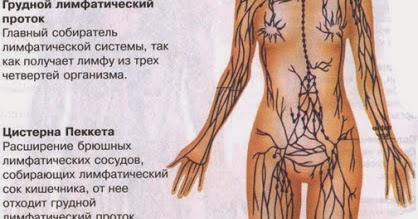

Изображения и схемы: как выглядит лимфа